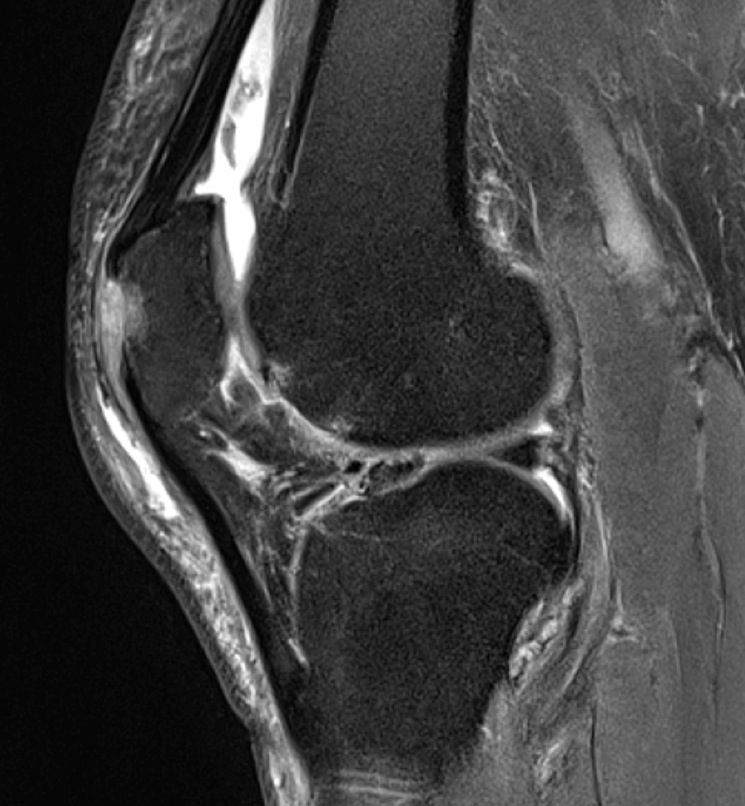

Figure 1 for case gout arthritis ( RID3567 )

Figure 1